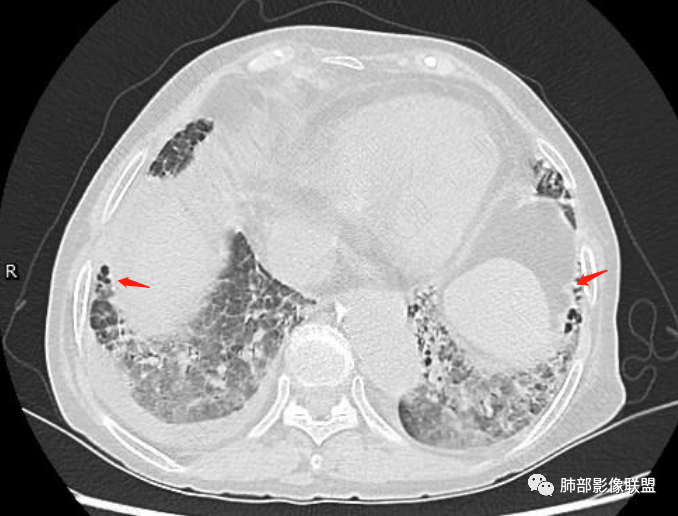

两肺叶后肋膈角区见多发蜂窝状结构破坏表现,双肺叶小叶间隔增厚,左肺上叶后段及舌段和右肺中叶胸膜炎性肉芽肿特点,双侧胸腔少量积液,有类风湿性关节炎治疗史,结缔组织相关性间质性肺病。

发热,有类风湿性关节炎、糖尿病基础病,长期口服激素及免疫抑制剂,双肺多发磨玻璃影及小叶间隔增厚,蜂窝影,支气管扩张考虑非特异性间质性肺炎存在,左肺上叶不规则结节影,周围长毛刺局部肺气肿,考虑慢性炎症,结合pct及crp升高考虑细菌感染,另真菌g升高考虑结合宿主因素,真菌感染需要积极排除。

老年,外阴溃疡加发热,感染指标明显有异常,血气分析,过度呼吸及低氧血症,宿主因素,糖尿病和激素,基础疾病RA。影像,双下肺体积有缩小,有蜂窝?双肺磨玻璃,多发结节,双侧胸水。树芽不明确。是否有旧片,这个患者有UIP背景,是否感染或者UIP急性加重,或者基础上合并肺栓塞及肺水肿?长期激素,没有提供CD4细胞亚群,存在2种情况,1,风湿病没有压制住,肺考虑CTD相关性间质改变,压制过猛,结合感染指标,奴卡是有可能的。激素加糖尿病,结核也带排,激素加磨玻璃加G实验阳性,PCP也带排,临床信息太少,进一步排查

老年女性,类风湿关节炎病史多年。发热。以两肺下叶为主弥漫磨玻璃及网格状透亮影,透亮度减低,局部小蜂窝状改变;两肺胸膜下散在几枚实性病灶;双侧胸腔积液。考虑RA-ILDNSIP

双下肺后肋膈角区见多发蜂窝,小叶间隔增厚,磨玻璃改变,,双侧胸腔少量积液,Crp明显升高,有类风湿性关节炎,糖尿病。甲氨蝶呤,托法替布治疗。会阴溃疡。考虑:1.免疫妥协2.pcp?巨细胞病毒?3.甲氨蝶呤致肺损伤?4.Ctd-ild.

两下肺多发蜂窝状表现,双肺小叶间隔增厚,双肺磨玻璃影及部分炎性肉芽肿表现,双侧胸腔积液,有类风湿性关节炎治疗史,结缔组织相关性间质性肺病。患者C反应蛋白和降钙素原都高,是否合并细菌感染

老年女性,外阴溃疡伴发热,有类风、糖尿病病史,血象及炎症指标高,G试验升高;影像:磨玻璃密度(中央分布为主)胸膜下蜂窝状改变心影增大、两侧胸腔少量积液;小叶间隔增厚,结节;考虑:1.中央分布为主的GGO需考虑:肺水肿、出血、PJP、肺泡蛋白沉着症;2.胸膜下间质性改变蜂窝肺,需考虑UIP、CTD-ILD,综合:两元论:CTD-ILD奴卡,或肺水肿

双肺下叶多发蜂窝影,双肺小叶间隔增厚,双肺磨玻璃影,双侧胸腔积液,有类风湿性关节炎,考虑结缔组织相关性间质性肺病,合并感染

①影像表现复杂:较弥漫间质性改变,对称磨玻璃密度为主,小叶间隔增厚,有一定重力分布趋势,未见明显纤维化,气囊及蜂窝位于肺边缘,未见典型“月弓征”。心脏影增大,双侧胸腔积液。

一般而言,如存在磨玻璃密度影浑浊,有重力分布趋势,肺表面蜂窝影,胸腔积液等等,并不常见于单纯PJP,除非其他因素叠加。

患者存在肺水肿应当是合理的解释。其他旁证还有,心脏影增大,肾小球滤过率降低,双侧胸腔积液等等……